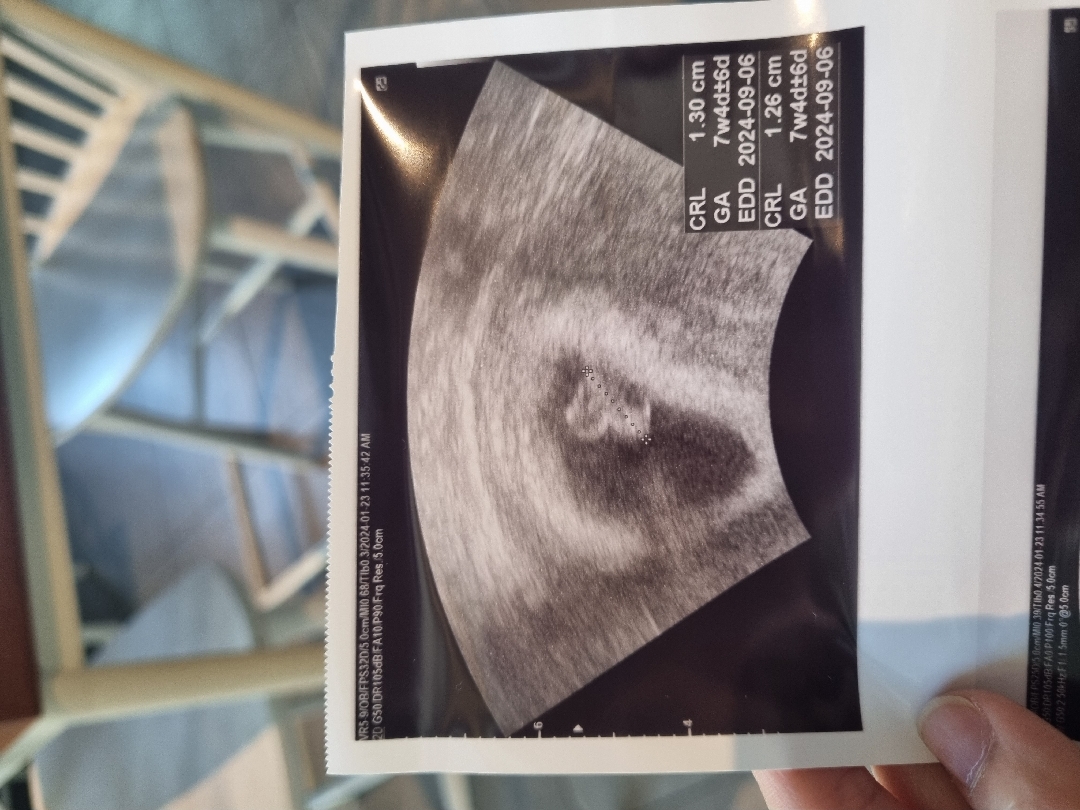

7주4일

작년에..고령임산부라서그런지...5주때 계류유산겪고 5개월만에 다시 찾아온 아가예요!!작년에는 느끼지못햇던 입덧 먹덧 배 콕...어제 밤 돌아다니면서 배가 콕해서 오늘 일주일만에 다시갓는데...이등신을하고있는 아가가 심장소리도 엄청크게 소리내고 펑펑울엇어요🥲